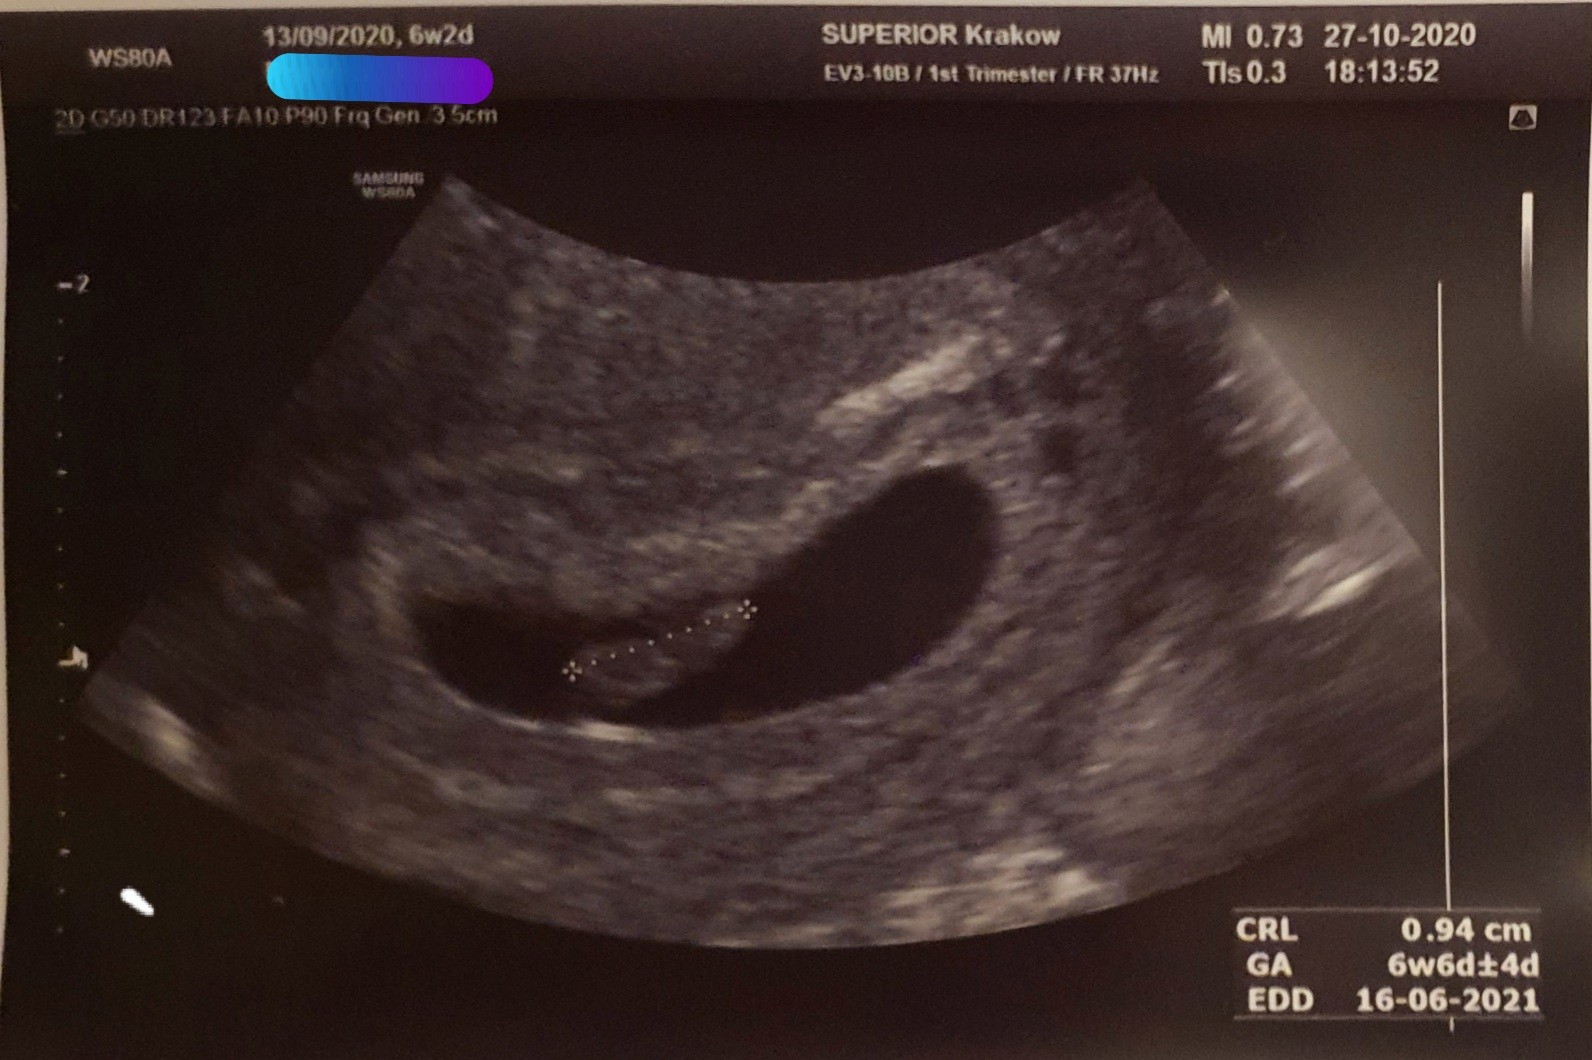

Dziewczyny ja już po mojej wizycie :) wszystko ok. Serducho bije. Tetno 146 :) kawał dzieciątka już jest. W opisie 9.8mm a ze zdjęcia 9.4mm wiec nie wiem czy lekarz sie walnął czy złapał jeszcze jakiś większy pomiar w miedzyczasie. Wg OM wychodzi 6+2, a wg USG 6+6. Pewnie to dlatego że mam krótkie cykle 24-25 dni. Lekarz powiedział że to już poważna ciąża. Przewidywany porod 16 czerwca 2021 plus/minus 4 dni. Wizyta mimo że prywatna i kosztowała "tylko" 280zł też z godzinną obsuwą, a że dotarłam do lekarza godzinę przed czasem to koczowałam na miejscu 2h :/ dopiero zaczełam obiad jeść przed chwilą.

• 20201027_210240.jpg

20201027_210240.jpg

174,5 KB · Wyświetleń: 98

• 20201027_210101.jpg

20201027_210101.jpg

288,6 KB · Wyświetleń: 96